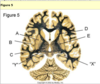

lesion to the optic tract leading to a field defect in both eyes. a nasal on right and temporal on left

damage to meyer’s loop in temporal fibers

this shows damage to meyer’s loop in temporal lobe usually caused by a tumor or stroke

loss of fibers after crossing over leading to side one eye losing vision on opposite side